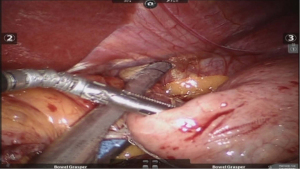

After placing the ports and the liver retractor, a thorough diagnostic laparoscopy is done. Omentum and transverse colon is lifted up to expose small bowel, and the duodeno-jejunal flexure/ligament of Trietz is identified. 75 cm of small bowel is measured from DJ flexure and it is hitched to stomach near lesser curvature at two sites using non absorbable sutures (Figure 3). Here, one should take care to keep proximal loop (biliopancreatic limb) on left side of patient. Beyond that point, another 100 cm of small bowel is measured distally and marked using non-absorbable suture at two sites 5 cm apart keeping proximal stitch small and distal stitch longer.